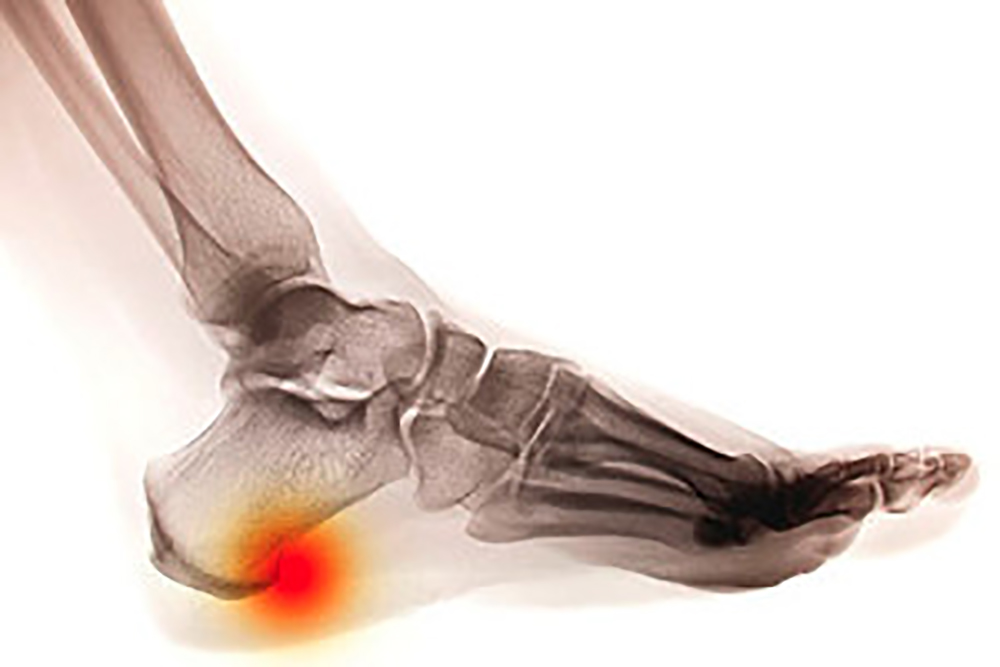

Plantar fasciitis is the inflammation of the thick band of tissue that runs along the bottom of your foot, known as the plantar fascia, and causes mild to severe heel pain.

Heel spurs are small, bony growths caused by excessive calcium deposits forming on the heel of the foot. These can grow on the bottom of the heel or the heel bone where the plantar fascia ligament attaches the heel to the toes. This connective tissue keeps the foot in a comfortable arch position, but a heel spur can damage the fibrous tissue and it will not be able to perform its job. In addition to causing every step one takes to be painful, heel spurs can cause long-term foot problems. Trying to purchase shoes that accommodate heel spurs can be an overwhelming task, yet it is imperative to wear proper footwear. When choosing footwear to alleviate pain and prevent further damage from heel spurs, it is crucial to look for shoes with firm rearfoots or backs of shoes. These are less apt to bend during movement and thus provide more support to the heel. Shoes should also have additional cushioning and a flexible forefoot that bends and stretches easily with movement. If you suffer from heel spurs, consult with a podiatrist who can help you with treating this condition, as well as suggest the best footwear to help with pain and prevention.

Heel spurs are formed by calcium deposits on the back of the foot where the heel is. This can also be caused by small fragments of bone breaking off one section of the foot, attaching to the back of the foot. Heel spurs can also be bone growth on the back of the foot and may grow in the direction of the arch of the foot.

Older individuals usually suffer from heel spurs and pain sometimes intensifies with age. One of the main conditions spurs are related to is plantar fasciitis.

Pain

The pain associated with spurs is often because of the weight placed on the feet. When someone is walking, their entire weight is concentrated on the feet. Bone spurs then have the tendency to affect other bones and tissues around the foot. As the pain continues, the feet will become tender and sensitive over time.